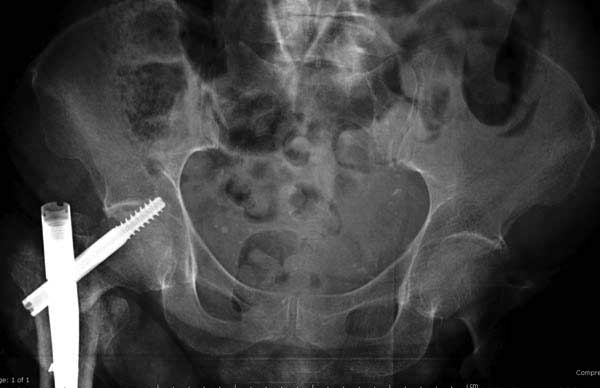

Первые снимки показывают технические погрешности установки DHS. Не была достигнута репозиция, конечность в флексии и шейка в ротации. Сегодня все меньше обращают внимание на параметры для оценки репозиции (S контуры Lowell в обеих проекциях и Garden Alignment Index, в норме 155 и 180 градусов), хотя такие простые тесты помогли бы дорепонировать смещение. Винт находится сзади в головке, что при нагрузке поменяет вектор и вместо компрессии в линии перелома срежет головку-Cut Out!

В зависимости от дистанции линии перелома и латерального кортекса надо использовать разной длины barrel, т.е. конец баррели не должен доходить до пределов перелома. Здесь конец длинного ствола упирается в медиальный фрагмент, что мешает созданию компрессии, а более короткий barrel создал бы запас для компрессии. В боковой пластине вместо 4х можно было ограничится двумя шурупами, потому что головка шурупа в 4.5 мм выдерживает давление до 350 кг.

Вторая операция- это фаза сохранения головки бедра. Желательно приложить все усилия и сохранить головку, но, как видно, “фиаско” продолжается. Здесь вместо нейтрализации сил между медиальной и латеральными сторонами была попытка удержать варус. Варус не удержать ни деротационными шурупами о котором говорили и не костными стружками вбитые в шейку, потому что вся нагрузка упирается в головку.